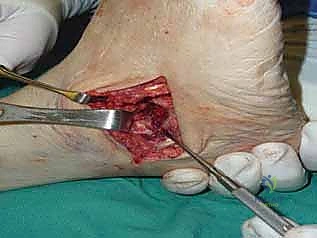

1. الشقوق الجراحية (Incision & Approach)

يتم إجراء شقين جراحيين للوصول إلى المفاصل الثلاثة:

* شق خارجي (Lateral Incision): للوصول إلى المفصل تحت الكاحل والمفصل العقبي المكعبي.

* شق داخلي (Medial Incision): للوصول إلى المفصل الكاحلي الزورقي.

يحرص الدكتور هطيف على حماية الأعصاب والأوعية الدموية الحساسة المحيطة بالمنطقة.

2. تحضير المفاصل وإزالة الغضاريف (Joint Preparation)

هذه هي الخطوة الأهم. باستخدام أدوات دقيقة، يتم كشط وإزالة جميع الغضاريف المتبقية (التالفة) من المفاصل الثلاثة وصولاً إلى العظم الإسفنجي النازف (Bleeding Subchondral Bone). يجب أن يكون العظم حياً وغنياً بالدم لضمان التئامه والتحامه مع العظم المقابل.